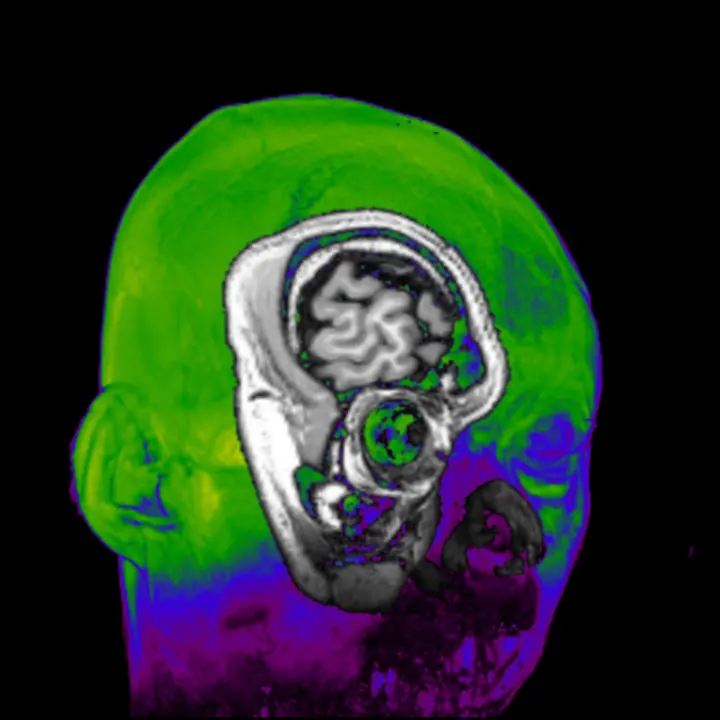

photo©Hanayuki Higashi 制作年 2018年 時間 16分(1分 x 16個) title: Daito Manabe + Kamitani Lab, Kyoto University and ATR "dissonant imaginary" 音を聴くことで変化する視覚野、連合野の 脳活動データを用いて画像を再構成する様子を可視化した作品。 マテリアル: オーディオビジュアル Kamitani Lab http:…